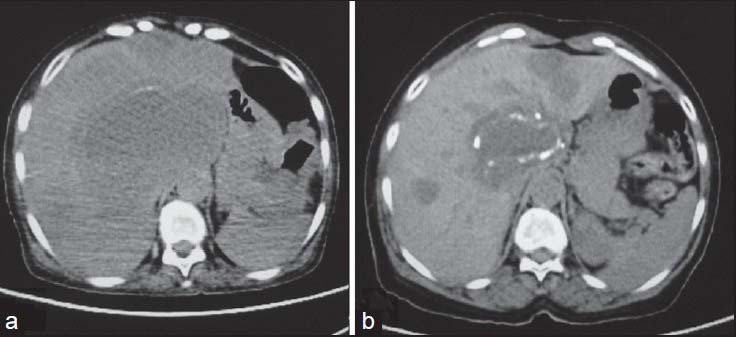

Complete surgical excision is the treatment of choice. Unlike carcinomas, resection of GISTs does not require wide bowel excision or lymphadenectomy as these tumors usually do not show lymph node metastases.[8] However, despite apparently complete resection with clear margins, the recurrence rate is high. Chemotherapy with imatinib mesylate, a tyrosine kinase inhibitor has been found to be highly effective in treatment of metastatic GIST. Imatinib mesylate has revolutionized the management of GIST. Now it is often used as the first-line treatment for unresectable, metastatic, or recurrent GIST. Although complete responses are rare, a large majority of patients with metastatic or inoperable GIST have either a partial response or disease stabilization after starting imatinib. Median survival rates have gone from <2>5 years since the advent of imatinib therapy.[11] Role of imaging also lies in response evaluation of patients treated with imatinib. Response to imatinib is characterized by decreased enhancement, resolution of the enhancing tumor nodules and a decrease in tumor neovascularity [Figures [Figures1616--20].20]. These changes are usually seen within 1-month of initiation of chemotherapy. Initially, tumors may enlarge during treatment due to intratumoral hemorrhage and myxoid degeneration. Enlargement with an overall decrease in tumor enhancement suggests a favorable response. Presence of new enhancing nodules within the tumor is consistent with recurrence.[12]

| Figure 18:Submucosal stomach gastrointestinal stromal tumors (GISTs) postsurgery — (a) axial contrast-enhanced computed tomography showing homogenously enhancing (arrow) stomach GIST (b) postsurgery, there is complete resection of the tumor with no evidence of recurrence (arrow)

| Figure 18:Submucosal stomach gastrointestinal stromal tumors (GISTs) postsurgery — (a) axial contrast-enhanced computed tomography showing homogenously enhancing (arrow) stomach GIST (b) postsurgery, there is complete resection of the tumor with no evidence of recurrence (arrow)